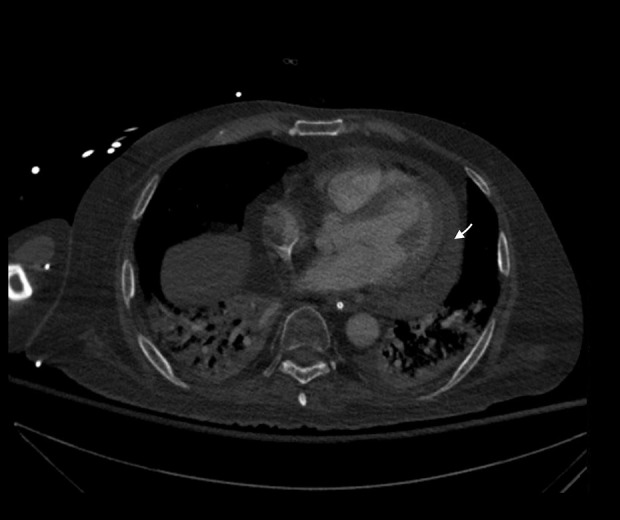

BACKGROUND Adenoviruses are double-stranded DNA viruses capable of causing a spectrum of diseases from mild respiratory infections to severe systemic illnesses. Disseminated adenovirus is evidenced by gastrointestinal, pulmonary, genitourinary, neurologic and even cardiac involvement. In immunocompromised individuals, adenovirus infections can become severe and are often associated with significant morbidity and mortality. CASE REPORT A 52-year-old man with a history of large granular lymphocytic (LGL) leukemia underwent haploidentical hematopoietic stem cell transplantation (HSCT). His course was complicated by the diagnosis of hemorrhagic cystitis with findings of adenovirus. His condition rapidly declined, necessitating Intensive Care Unit (ICU) admission. Comprehensive workup identified adenovirus in the serum and cerebrospinal fluid (CSF), bronchoalveolar lavage fluid, and positive stool adenovirus. Echocardiographic evaluation revealed a moderate pericardial effusion requiring pericardiocentesis. Unfortunately, adenovirus testing of the aspirate could not be performed. Given the diagnosis of disseminated adenovirus infection, treatment with cidofovir and probenecid was initiated, but despite these interventions, the patient's status continued to deteriorate complicated by multiorgan failure and refractory shock. CONCLUSIONS This case underscores the complexity of diagnosing disseminated adenovirus, particularly given the potential for multiorgan system involvement. Early recognition is essential, such as viral polymerase chain reaction (PCR), playing a critical role in the identification and monitoring of infection. The case further emphasizes the pressing need for continued research into novel antiviral therapies and preventive measures to mitigate the risk of adenovirus in this vulnerable population.